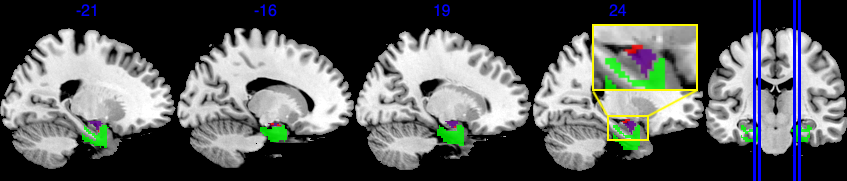

The amygdala region is part of the limbic system. They are responsible for detecting danger and negative emotions, and play an important role in behavior, emotional control, and learning (Bzdok et al., 2013). The emotion task fMRI data in UK Biobank is based on emotion tasks where participants are asked to identify faces with negative emotions. Hence we expect the amygdala region to play an important role. The amygdala region is a small area in the brain, as shown in Figure 4(a), containing 380 voxels out of a total of 121,865 voxels.

Based on the results shown in Figure 4, SBIOSimp identifies a large proportion of voxels in the amygdala region to be active. Numerically, SBIOSimp identifies 324 out of 380 voxels in both the left and right amygdala to be active with . From the highlighted box in Figure 4(b), the active voxels mostly concentrate on the direction where the amygdala region connects to the parahippocampal gyrus, anterior division. The anterior portion of the parahippocampal gyrus is involved in complex emotive processes and has significant interconnectivity with other cortical limbic structures and the amygdala (Kaas, 2016). Figure 4(c) shows the yellow-shaded area within the amygdala in which voxels are associated with at least 50% decline in the brain signal intensity for 10-year increase in age from 50.